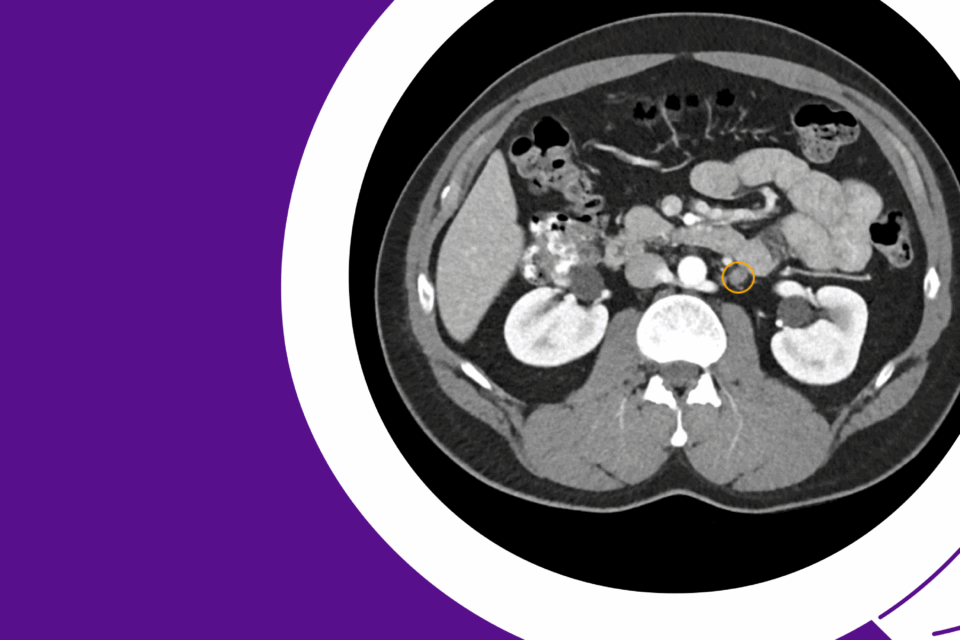

Robotic Management of Giant Hydronephrosis & Contralateral UPJ Obstruction

Dr. Brian W. Chao details his approach to robotic nephrectomy and pyeloplasty for incidentally discovered giant hydronephrosis and contralateral UPJ obstruction.